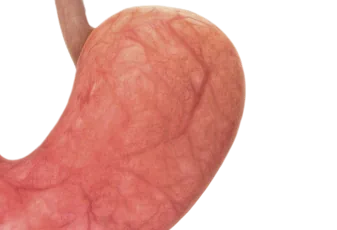

בדיקת גסטרוסקופיה

בדיקת גסטרוסקופיה - המדריך עם כל המידע הרפואי והמעודכן בבדיקת גסטרוסקופיה מוחדר צינור גמיש בקוטר של כסנטימטר אחד דרך הפה אל הוושט וממנה אל הקיבה והתריסריון (חלקו הראשון של המעי הגס, האזור בו מבוצע רוב תהליך העיכול). בקצה מכשיר הבדיק